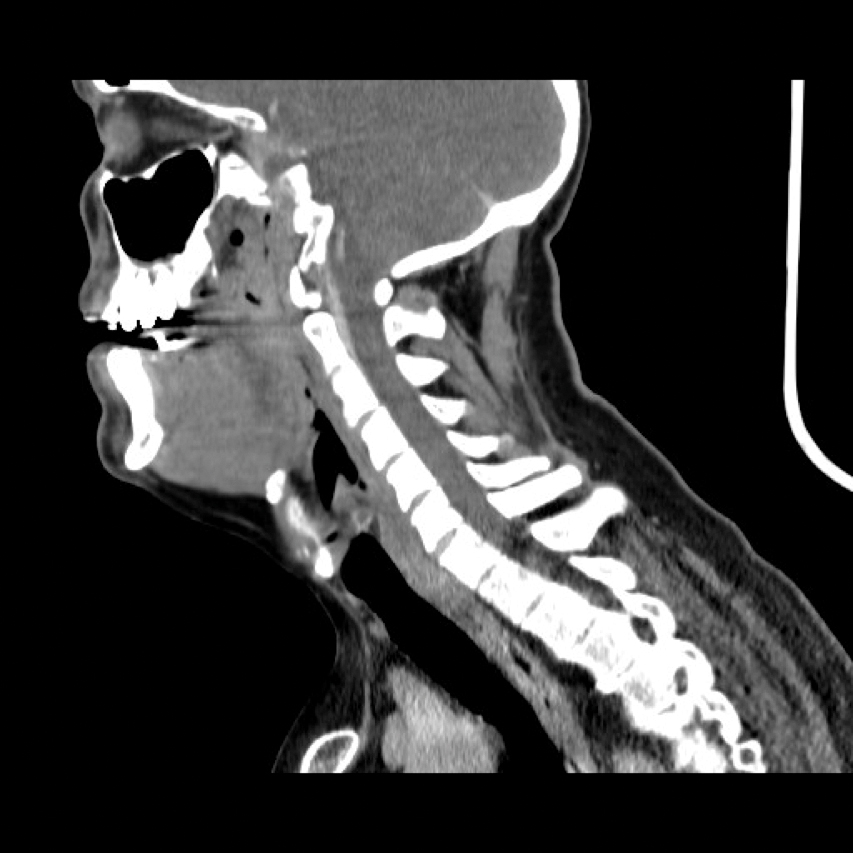

Initial investigations included blood tests and an orthopantomogram (OPG). The INR was 26. The OPG showed a large periapical radiolucency associated with the lower left lateral incisor which had previous endodontic treatment but no dental / bony cause for his advanced neck swelling was identified. A CT scan (Figure 1, 2 and 3) indicated that there were soft tissue density masses present within the floor of the mouth. They most likely represented a haematoma but an abscess could not be excluded. The airway was markedly compromised. He was immediately planned for surgical intervention with the input of the haematologist and anaesthetist, along with urgent treatment to reverse the effects of Warfarin.

Figure 2 (sagittal view).

Figure 3 (transverse view): CT showing a large indistinct mass / swelling of the submandibular and submental spaces with compression and deviation of the airway. Not a typical appearance of an abscess.